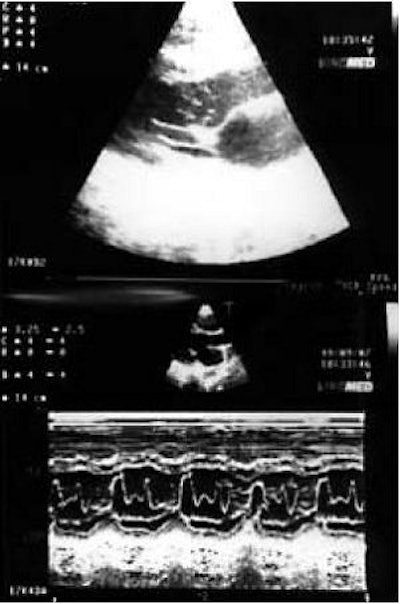

![]() |

| Seventeen-year-old asymptomatic basketball player. Rest ECG was normal except for rare ventricular escape beats, singled and coupled. Two-dimensional transesophageal echocardiography (TEE) of the left parasternal short-axis aortic view. Panel B (below) clearly shows the right coronary artery (RCA) originating abnormally from the left sinus of the Valsalva, close to the left coronary ostium and the left main (LM), and running around between the aorta and pulmonary artery; for comparison, panel A (above) shows the normal position of coronary ostia in a 16-year-old water polo player. |